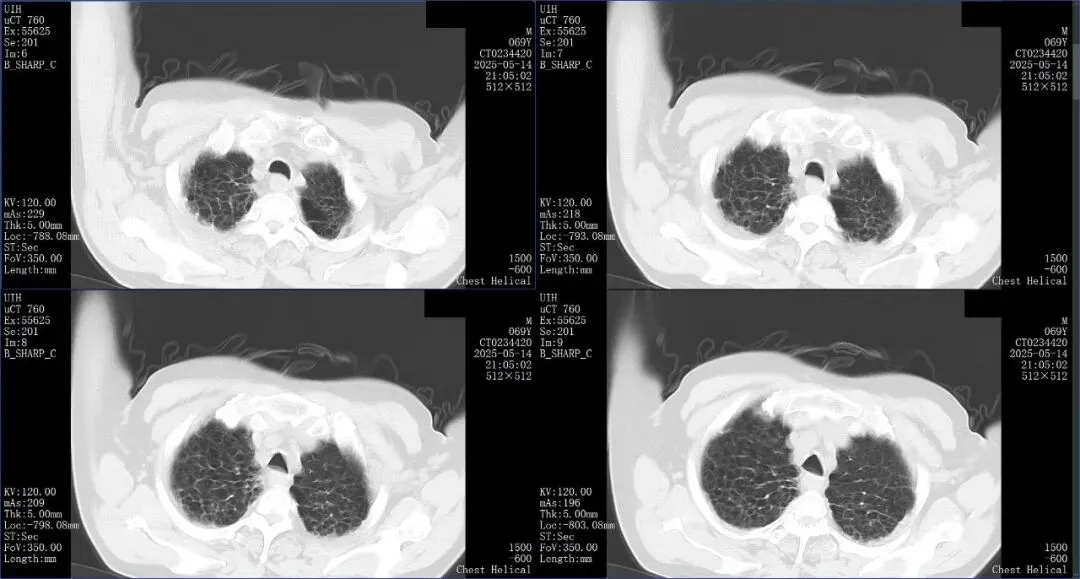

上图是一例外源性脂质性肺炎,不是蜂窝征。